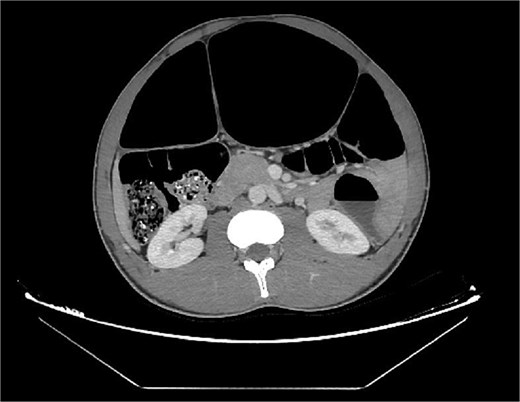

Abdominal radiography demonstrated classic features of sigmoid volvulus including dilated colonic loops, multiple air-fluid levels, and the characteristic coffee bean sign with absence of rectal gas. Computed tomography (CT) imaging (Figs 1 and 2) confirmed the diagnosis, revealing large gas-filled loops (maximum diameter 100 mm) without haustration and the typical mesenteric whirl sign, consistent with closed-loop obstruction. Initial management with colonoscopic decompression was attempted but proved unsuccessful, with persistent abdominal distension and tympani necessitating surgical intervention. Intraoperative findings confirmed a dolichosigmoid with mesenterico-axial volvulus, requiring sigmoid colon resection with creation of a double-barrel stoma using the Bouilly-Volkmann technique. Pathological examination of the resected specimen (30 cm in length, 491 g in weight) revealed flattened, hemorrhagic mucosa with vascular congestion and edema (Fig. 3). Microscopic analysis identified numerous Schistosoma eggs of varying morphology (Fig. 4A and B) within the submucosa and muscular layers, accompanied by granulomatous inflammation (Fig. 4C) and dense eosinophilic infiltrates. Chronic changes including eosinophilic microabscesses and calcified eggs were also noted (Fig. 5).

Axial abdominal CT scan revealed dilated gas-filled loops with lack of the haustration.